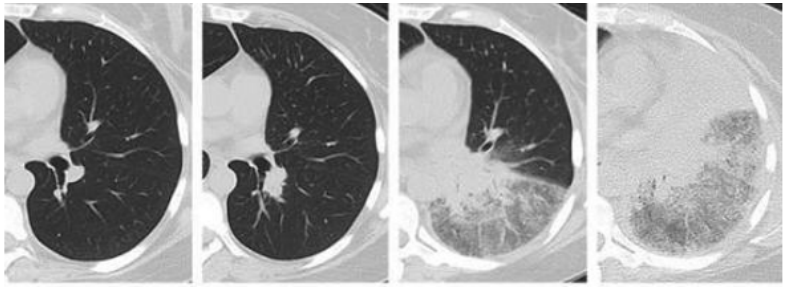

病毒性肺炎是由各种呼吸道病毒感染引发的肺实质炎症,容易并发呼吸衰竭,常见于幼儿(<5岁)和年龄>50岁的成人。WHO数据显示:社区获得性肺炎(CAP)中病毒性肺炎占20%~40%,在ICU中比例稍高,为30%~40%。常见病毒性肺炎的病原体包括流感病毒、鼻病毒、呼吸道合胞病毒、腺病毒、人偏肺病毒、巨细胞病毒、冠状病毒等。病毒性肺炎的常见影像学特征如下:图1所示为COVID-19的高分辨率CT(HRCT):在急性期,图1A为双肺弥漫性磨玻璃影(GGO),图1B为小叶周围型,图1C和D表现为亚急性间质性肺炎,GGO减少,主要为胸膜下局灶性实变和小叶间/小叶内间质增厚。图2A-C显示了一例与COVID-19间质改变相似的甲型流感病例:GGO主要分布在胸膜下和双侧,呈小叶周围性分布。图2D为同一患者的仰卧位胸片,可见弥漫性肺间质受累。图3A-D为一例H1N1相关肺炎并发急性呼吸窘迫综合征(ARDS)的影像,可见弥漫性、双侧GGO以及牵拉性支气管扩张。图4A显示了一例急性腺病毒肺炎,具有典型的多灶性和大叶GGO,图4B-C显示其导致的长期后遗症——Swyer–James综合征的表现。图5所示为一例疱疹病毒性肺炎,可见双侧分布呈斑片状的GGO(主要位于两肺上叶)。一项基于对美国大规模人群分析的前瞻性多中心研究显示,病毒性肺炎的患病率和发病率随年龄而异,其累积发生率约为22%。研究纳入2222例儿童,其中66%(共1472例)报告有病毒感染,在155例(7%)病例中发现病毒和细菌合并感染。事实上,呼吸道病毒、腺病毒和人偏肺病毒在5岁以下儿童中比较常见。在同一研究的2259例成年人患者中,只有853例(38%)患者检测到病原体,530例(23%)患有病毒性肺炎,59例(3%)发现合并感染。